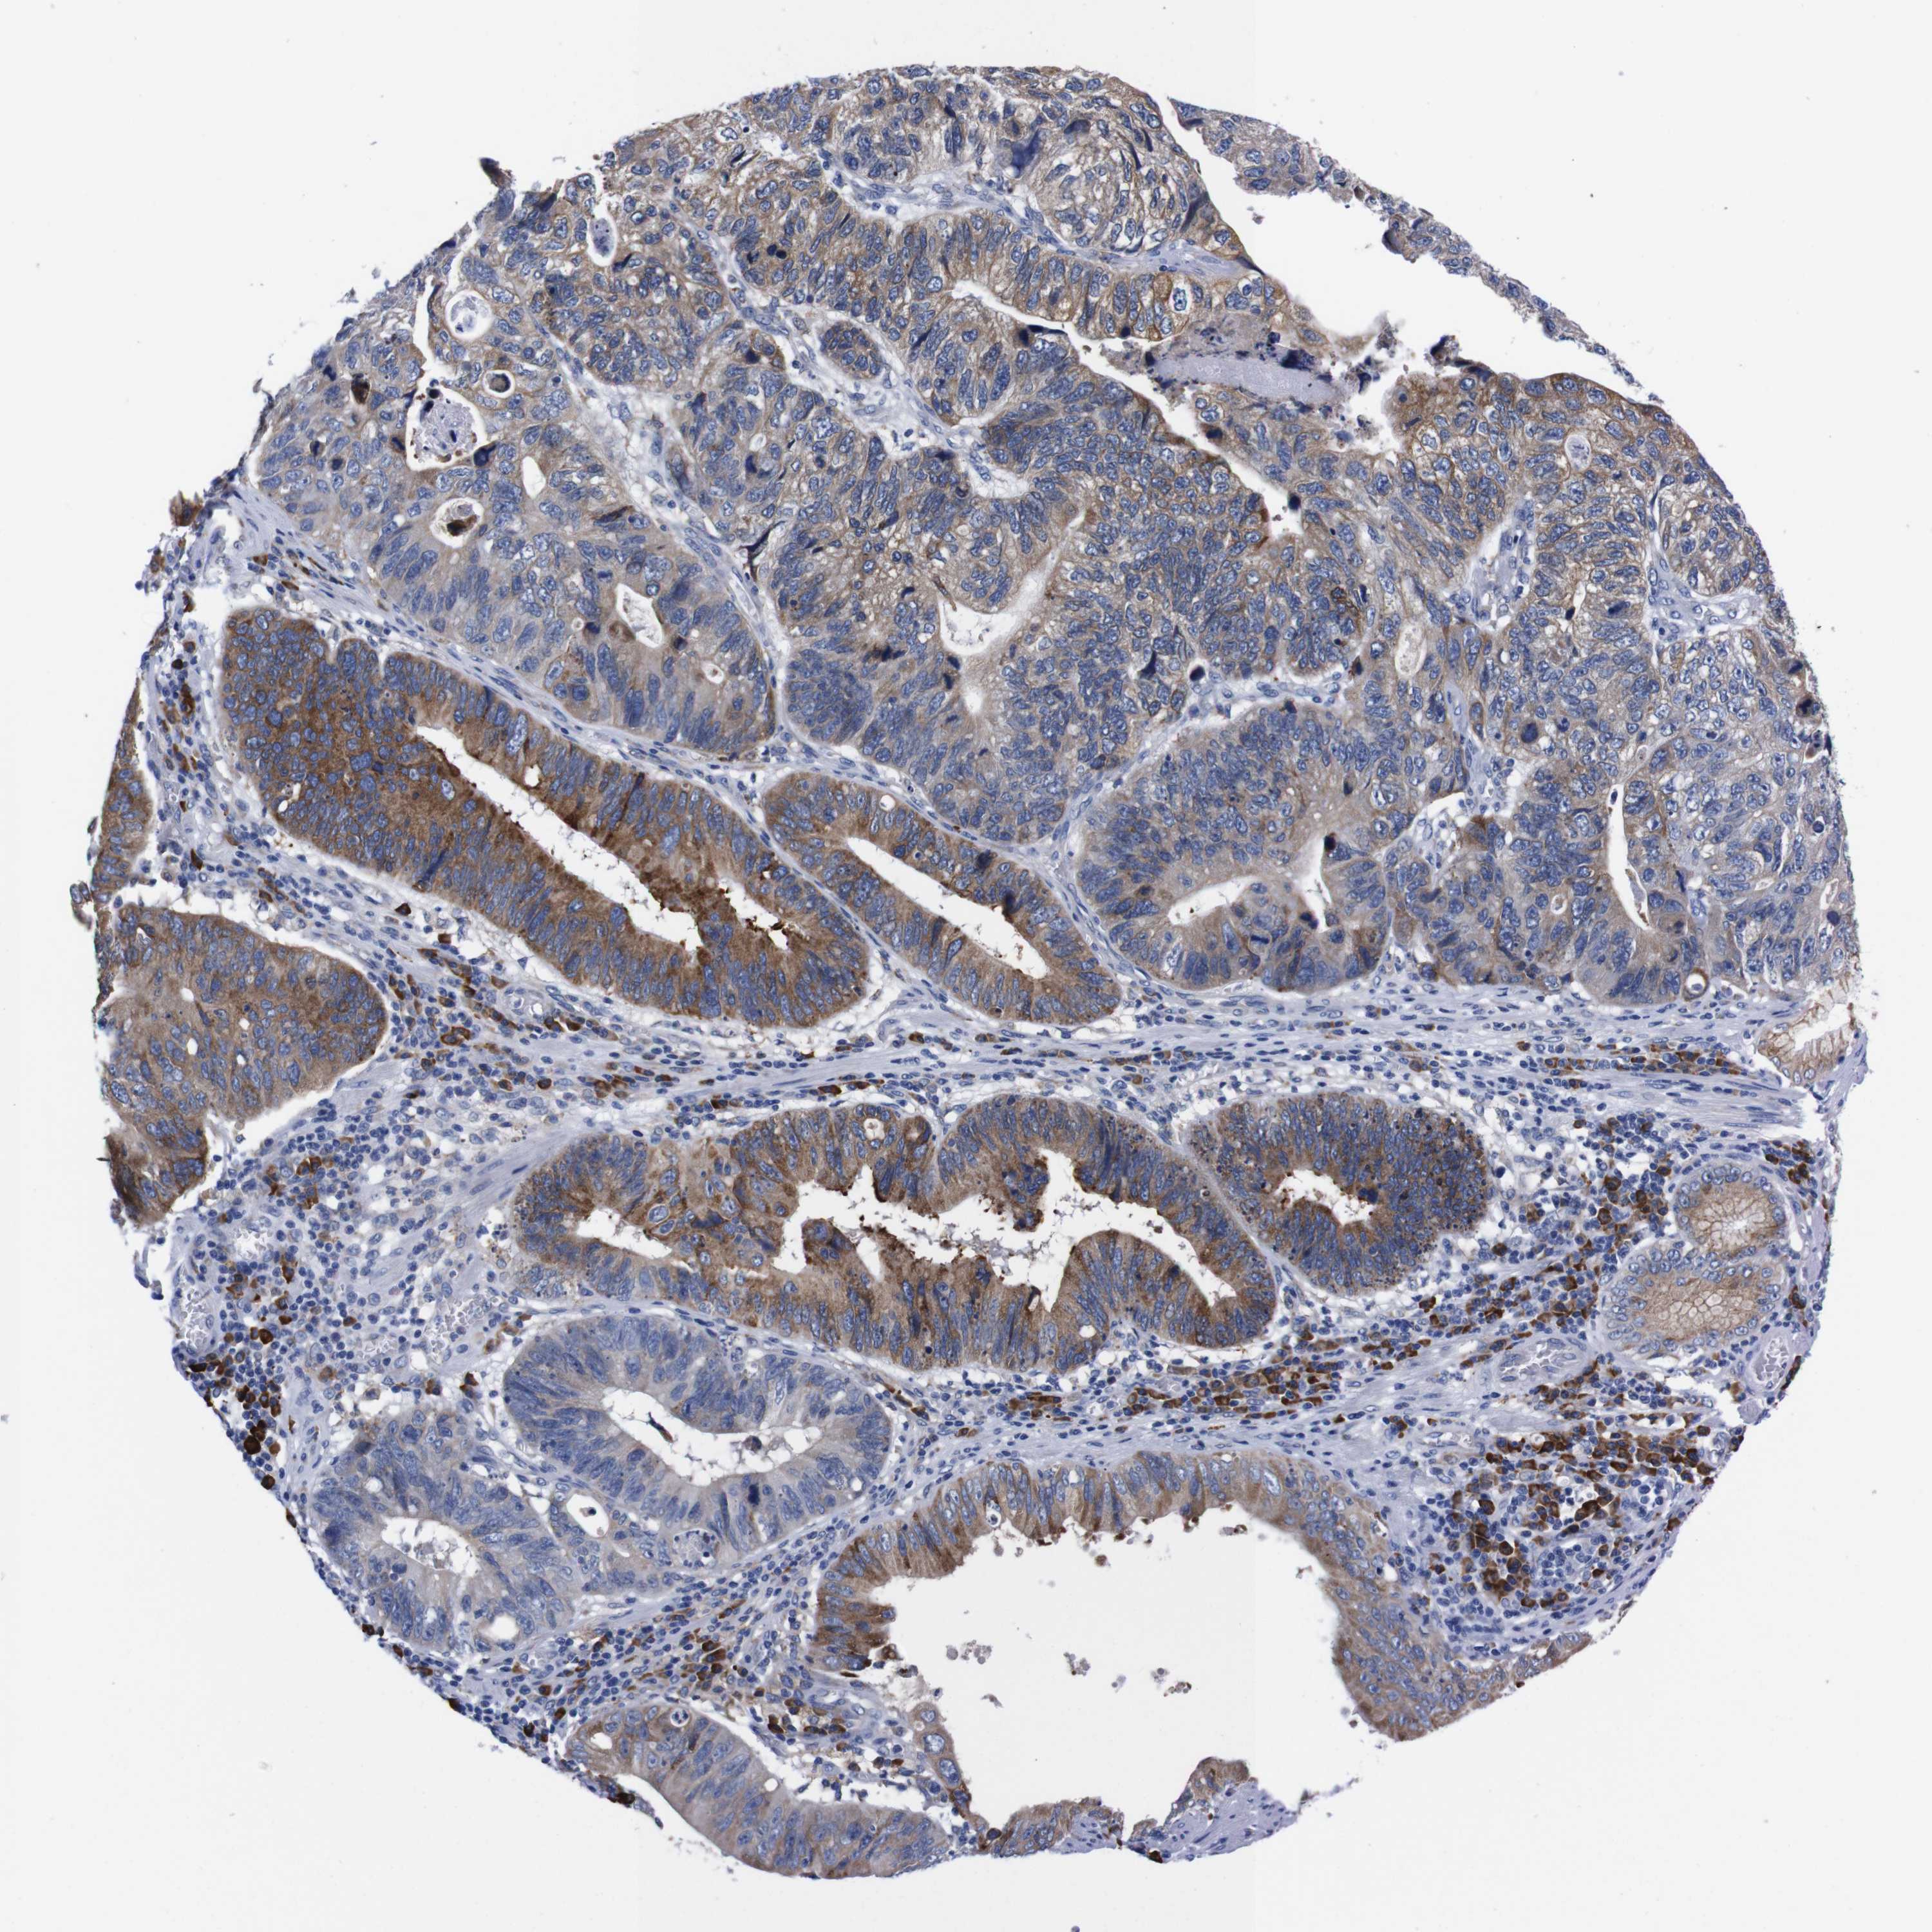

STOMACH CANCER - Protein expressioni

A mouse-over function shows sample information and annotation data. Click on an image to view it in a full screen mode. Samples can be filtered based on level of antibody staining by selecting one or several of the following categories: high, medium, low and not detected. The assay and annotation is described here.

Antibody stainingi

Antibody staining in the annotated cell types in the current human tissue is reported as not detected, low, medium, or high, based on conventional immunohistochemistry profiling in selected tissues. This score is based on the combination of the staining intensity and fraction of stained cells.

Each image is clickable and will lead to virtual microscopy that enables deeper exploration of all samples and also displays staining intensity scores, fraction scores and subcellular localization as well as patient and tissue information for each sample.

Antibody HPA013994

Antibody HPA013995

Staining

High

Medium

Low

Not detected

Intensity

Strong

Moderate

Weak

Negative

Quantity

>75%

75%-25%

<25%

None

Location

Nuclear

Cytoplasmic/membranous

Cytoplasmic/membranous,nuclear

Adenocarcinoma, NOS

Adenocarcinoma, High grade